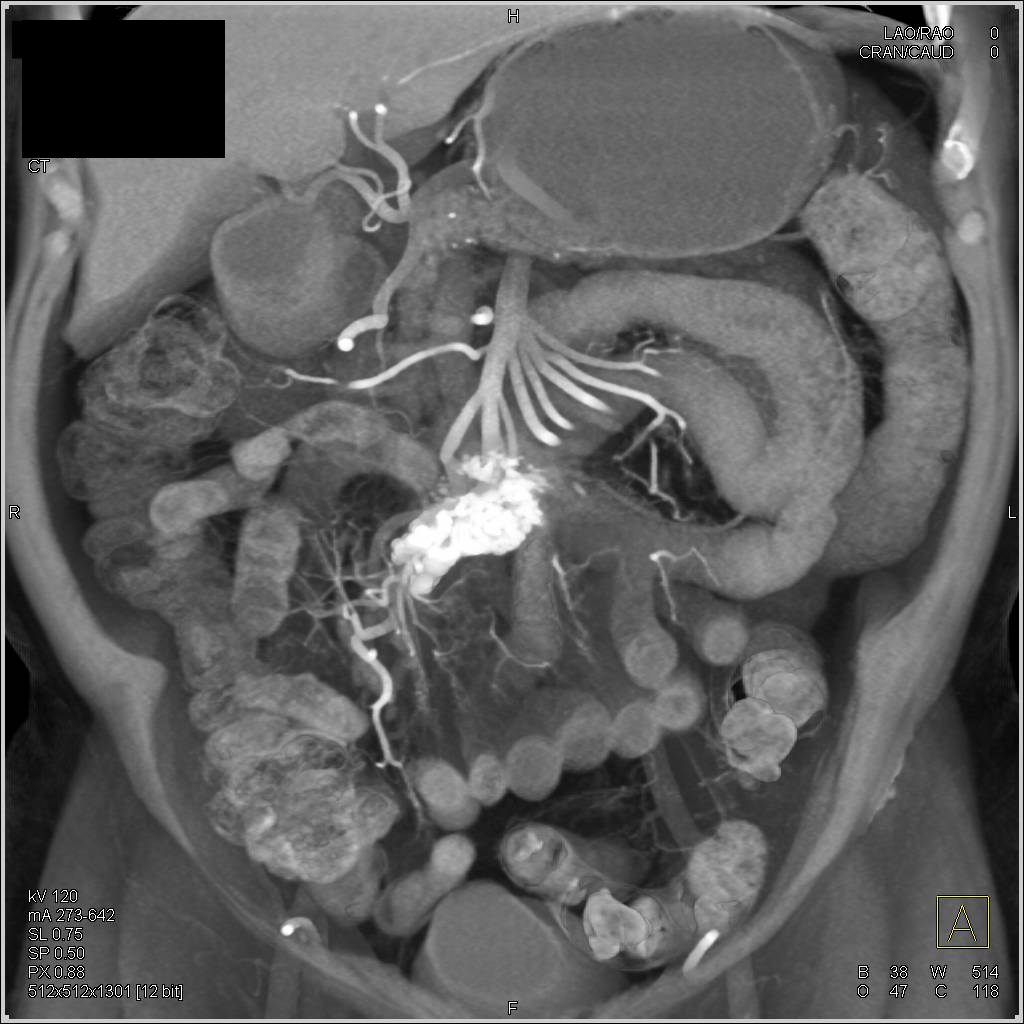

Crohn's Disease Terminal Ileum with Comb Sign